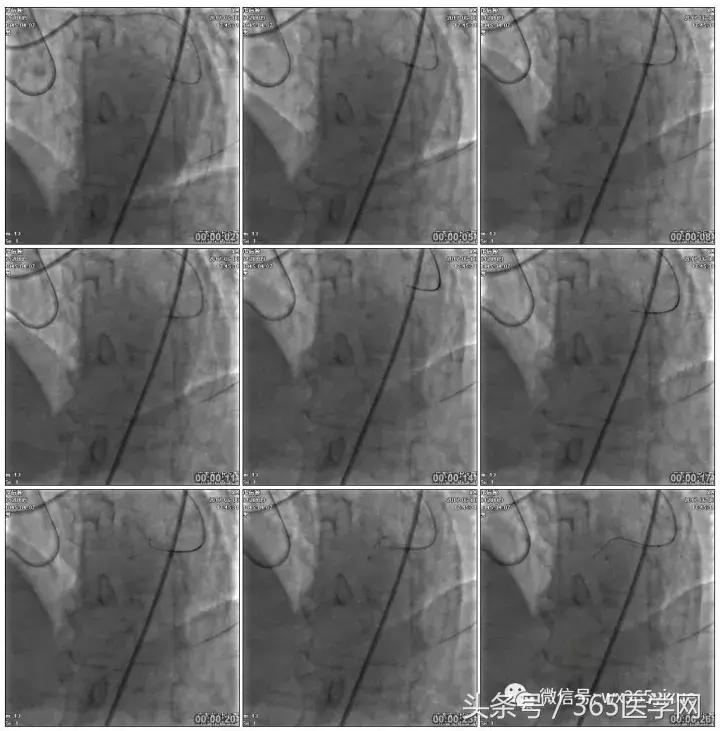

首先:IVUS指导下干预LAD

4.0mm*13mm药物支架

第二步:处理LCX

Fielder XT-A,Gaia First ---在微导管支撑下通过闭塞病变

LCX植入支架

2.0*10mm球囊

2.75*22mm药物支架